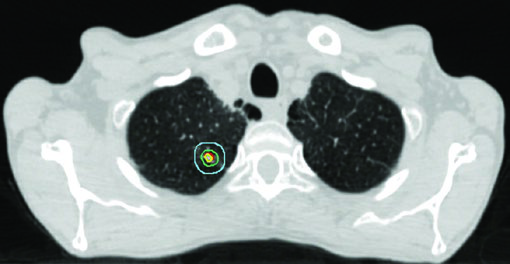

SBRT no CPNPC estádio inicial: precisão máxima

SBRT é o tratamento de escolha para CPNPC estádio I em pacientes inoperáveis e cresce como alternativa em operáveis de alto risco. O objetivo é BED > 100 Gy no tumor, com dose mínima possível nos tecidos normais circundantes.

A expansão iGTV → iCTV no estádio inicial é pequena: 0 a 0,2 cm. O raciocínio é que, no tumor pequeno e periférico, a extensão microscópica é mínima e a margem de setup domina a expansão final. A margem PTV adicional depende da tecnologia de IGRT disponível.

A árvore brônquica proximal (PBT) — definida como os 2 cm distais da traqueia, carina, brônquios principais, brônquios lobares e os primeiros segmentos dos brônquios segmentares — é a estrutura mais crítica no SBRT. Define-se uma zona de não irradiação (NFZ) de 2 cm além da PBT. Tumores dentro ou adjacentes à NFZ são considerados centrais e demandam fracionamento menos ablativo.

Os esquemas de dose variam por localização:

- Periférico: 54 Gy/3fx (18 Gy/fx), 48 Gy/4fx (12 Gy/fx), 50 Gy/4fx ou 50 Gy/5fx

- Central: 50 Gy/5fx, 70 Gy/10fx ou 60 Gy/8fx

A dose máxima em ponto da PBT é restrita a 55 Gy em qualquer esquema. A Figura 13.2 do texto mostra três casos de estádio inicial: tumor periférico clássico tratado com 54 Gy/3fx, tumor próximo à PBT com 48 Gy/4fx e tumor central com 50 Gy/5fx.